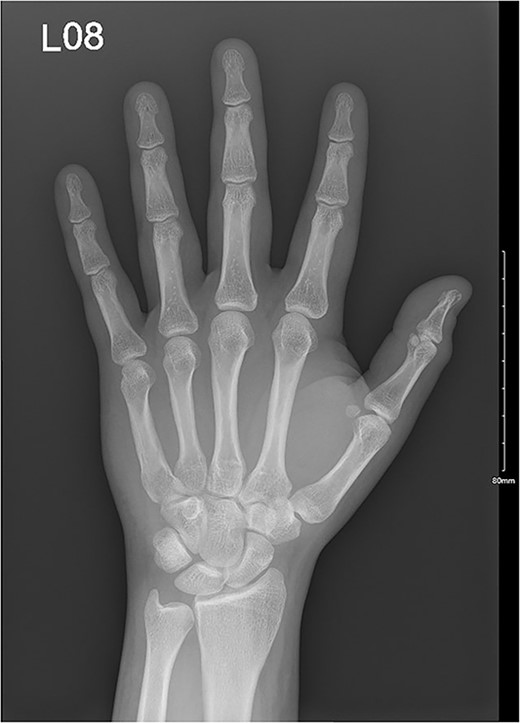

A 32-year-old male presented to the emergency department with a painful, discolored, and edematous left thumb following spontaneous deployment of his automobile’s airbag. On physical examination, the thumb’s range of motion (ROM) was reduced because of pain. Radiography showed a tuft fracture of the thumb’s distal phalanx (Fig. 1). The patient was managed conservatively with a Zimmer splint and followed-up 1 week later. Magnetic resonance imaging (MRI) was obtained to assess for the presence of ligamentous injury showed complete tearing and proximal retraction of the distal attachment of the ulnar collateral ligament in (Fig. 2), so the patient was given a thumb spica and was booked for surgery. In the operating room, the ulnar collateral ligament was identified and was indeed completely avulsed from its distal attachment site. The ligament was repaired using the Kessler tendon repair maneuver, ultimately ending with the thumb flexed 30° at the metacarpophalangeal (MCP) joint. This patient was followed-up for 103 days after his first presentation. On his final clinic visit, the thumb was stable, the wound was fully healed, and full ROM was regained.

A comminuted slightly displaced fracture of the tip of the left fifth distal phalanx.